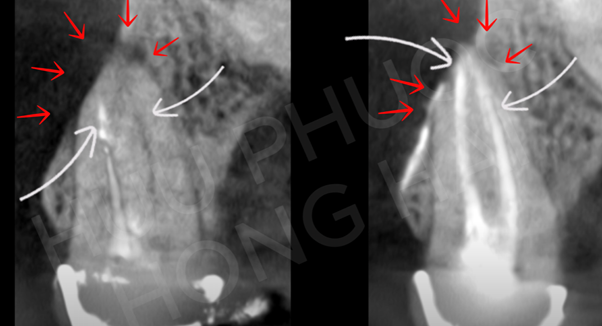

Một răng cối lớn hàm trên đã điều trị nội nha từ nơi khác nhưng thất bại bị nhiễm trùng quanh chóp (A), đến giảng viên NTTU điều trị nội nha lại thành công (B). Ca lâm sàng điều trị nội nha lại do BSNT.CKI. Lê Hồng Hải và BSNT.CKI. Huỳnh Nguyễn Hữu Phước – Giảng viên NTTU điều trị.